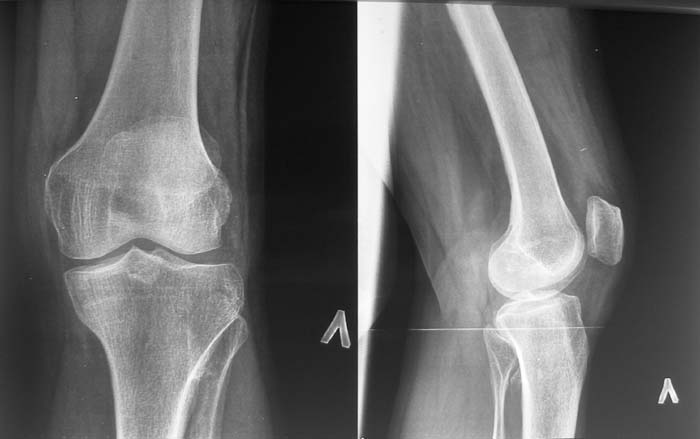

Женщина, 55 лет. С 2002 года - гонартроз. В настоящее время - боли в коленном суставе, стартовые боли, иногда в ночное время (проходит <от перемены положения ноги>).

Принимает НПВС, артрон-комплекс, внутрисуставно гиалган. Ревмопробы отрицательные. На рентгенограмме отметили сужение шейки малоберцовой кости, на спиральной КТ - экзостоз? Ваше мнение о целесообразности операции (велика вероятность повреждения нервов), предварительной биопсии?Спасибо! С уважением, А.В.Владзимирский Донецкий НИИ травматологии и ортопедии Донецк, Украина

Насчет протезирования коленного сустава - при таком сохранном суставе навряд ли можно согласиться и совершенно согласен с Яковом, что надо искать источника боли сканированием или магнеторезонансными исследованиями.

Действительно, надо бы определиться в причине болевого синдрома. Подобные остеомы, как правило, немые. Болевой синдром может быть связан с околосуставнойт патолоией (например, поражение "гусиной лапки") или внутрисуставной. По R - граммам сустав очень даже сохранный (протезировать его явно нет необходимости), а отвергнуть внутрисуставную патологию или сразу ее максимально устранить поможет артроскопическое вмешательство. Повреждения менисков частенько симулируют остеоартроз.

Суставная щель на вид очень даже приличная. Мне кажется у больной есть варусная деформация колена, и возмможно с этим связано дегенаративное поражение медиального мениска и вся клиническая картина. Если это так, то эндопртезирование это слишком! Может что полегче: артроскопия и медиальная плюс-остеотомия.

Экзостоз скорее всего случайная находка, но динамического наблюдения безусловно требует.